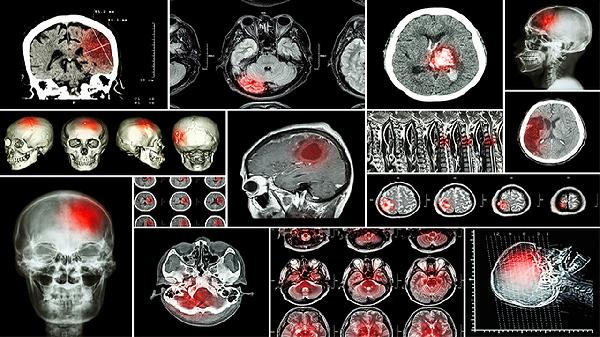

腦白質(zhì)發(fā)育不良的癥狀主要有運(yùn)動(dòng)障礙、認(rèn)知功能下降、語(yǔ)言發(fā)育遲緩、視力異常、癲癇發(fā)作等。腦白質(zhì)發(fā)育不良可能與遺傳因素、圍產(chǎn)期缺氧、感染、代謝異常、外傷等因素有關(guān),通常表現(xiàn)為肌張力異常、平衡能力差、學(xué)習(xí)困難等癥狀。